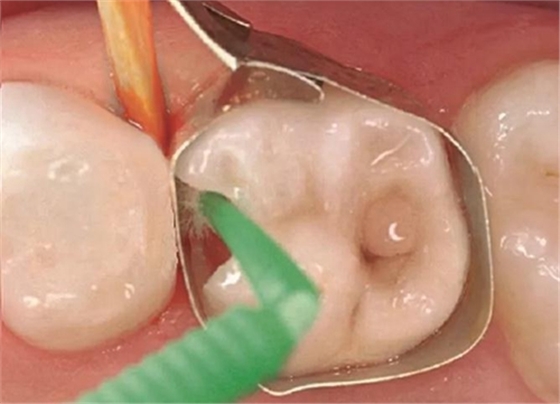

圖5:用Prime&Bond NT (Dentsply De Trey) 處理窩洞,作用時間為20秒,然后輕吹至少5秒并光固化10秒

圖6:在取下成行片之前用復(fù)合體(Dyract, Dentsply De Trey)填充窩洞并固化